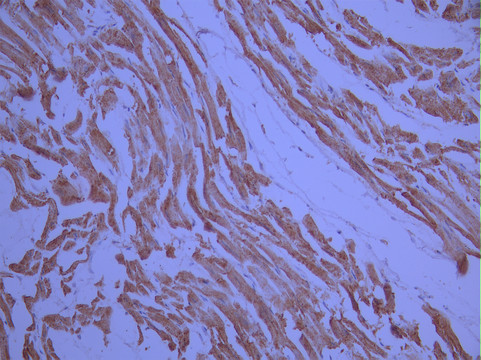

IHC image of CSB-RA212222A0HU diluted at 1:100 and staining in paraffin-embedded human heart tissue performed on a Leica BondTM system. After dewaxing and hydration, antigen retrieval was mediated by high pressure in a citrate buffer (pH 6.0). Section was blocked with 10% normal goat serum 30min at RT. Then primary antibody (1% BSA) was incubated at 4°C overnight. The primary is detected by a Goat anti-rabbit polymer IgG labeled by HRP and visualized using 0.05% DAB.